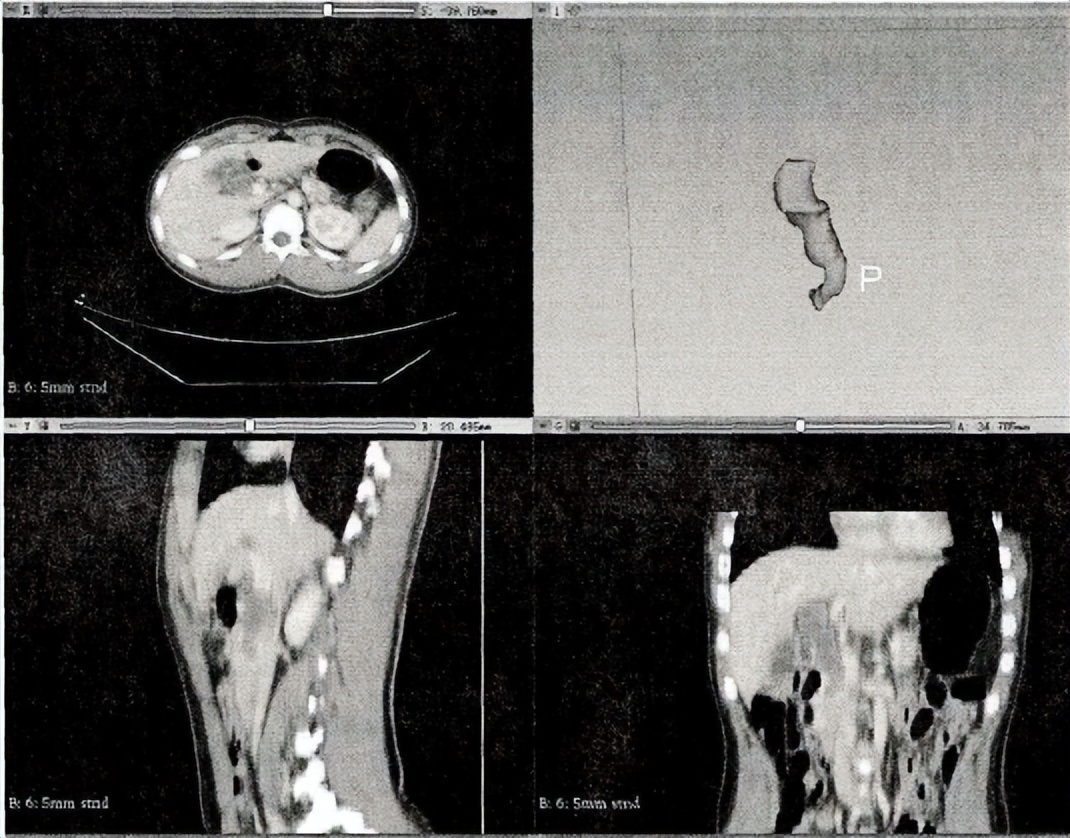

两名对患者的临床结果不知情的放射科医生,他们通过以下方式描绘了胆总管的感兴趣区域(ROi):使用在开源软件3-DsLiCer运行的Segmmert Editor程序,逐层手动勾画显影的胆总管及其内容物,然后在软件中形成3D的感兴趣区域。

3D感兴趣区域勾画示意图